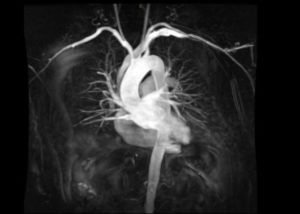

Пример томограмм МРТ сердца и сосудов

Магнитно-резонансная томография сердца и сосудов – это высокоинформативный метод, позволяющий выявить патологические изменения миокарда, коронарных артерий, перикарда.

МРТ основано на использовании магнитного поля, которое создает резонанс атомов водорода, которые искажают радиочастотный сигнал. Специальные датчики улавливают преобразованные импульсы. Программа обрабатывает изображения, создает пространственную модель.

Визуальное отображение модели позволяет изучать самые мельчайшие детали, тонкие анатомические элементы сердечных клапанов.